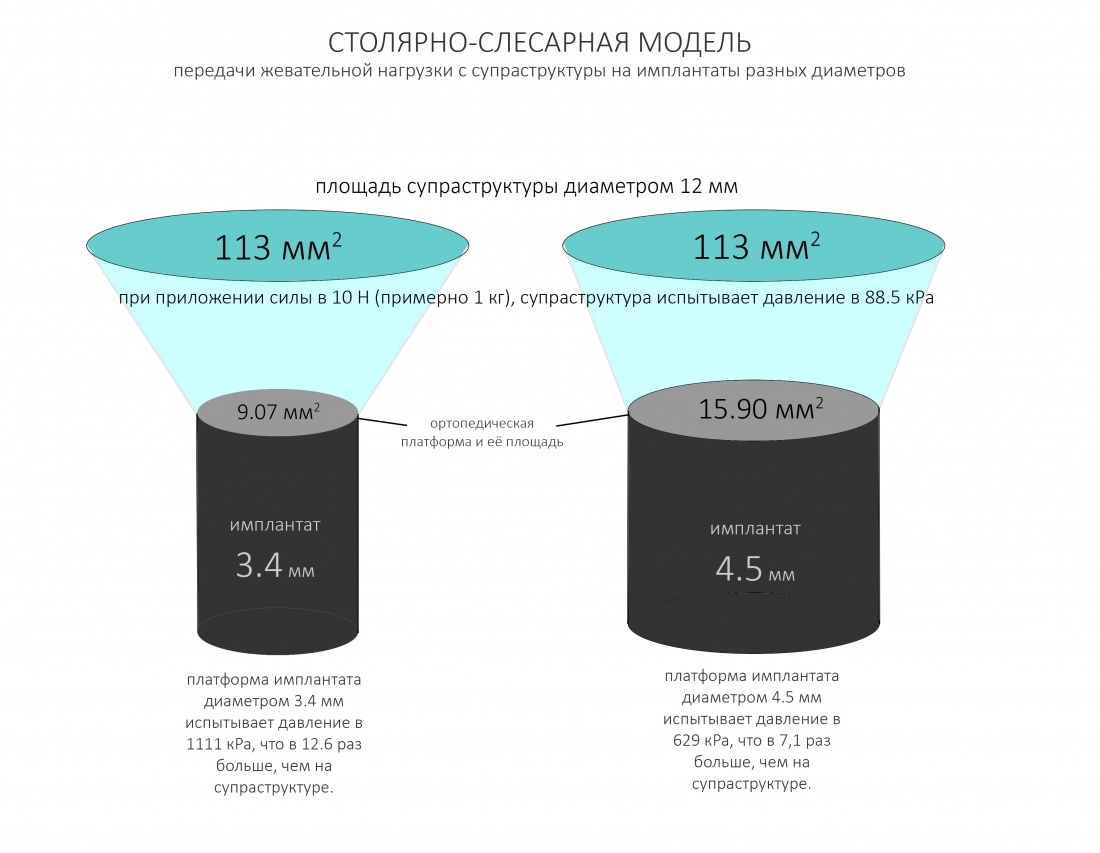

Причина того, что имплантаты с единой ортопедической платформой могут иметь разные диаметры, очень проста и понятна. Тонкий имплантат под действием нагрузки будет гнуться и деформироваться, в отличие от большего по диаметру. Тонкий имплантат будет менее равномерно передавать получаемую нагрузку на окружающую костную ткань. Это очень легко продемонстрировать на простой столярно-слесарной модели:

Вот почему имплантологическое правило #2 справедливо даже для имплантатов с единой платформой, хотя может показаться, что подбор их по диаметру не столь важен. Инструкция к Dentium это подтверждает.